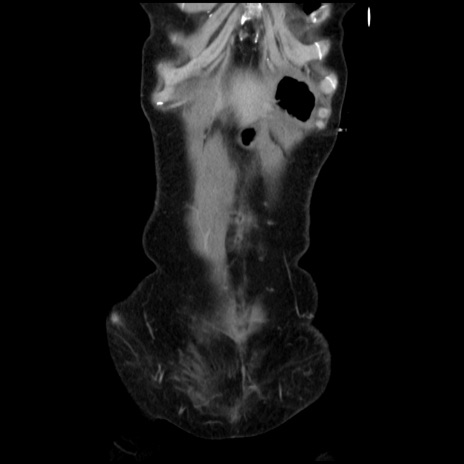

症例32(冠状断像)

【症例】40歳代 女性

【主訴】上腹部痛、嘔気・嘔吐

【現病歴】約9時間前頃から急に上腹部痛、嘔気、嘔吐が出現。改善しないため救急要請。

【既往歴】子宮頚癌(広汎子宮全摘術、放射線療法)、腸閉塞

【身体所見】腹部:平坦、軟、腸雑音亢進、上腹部を中心に腹部全体に圧痛あり。

【データ】WBC 8400、CRP 0.03